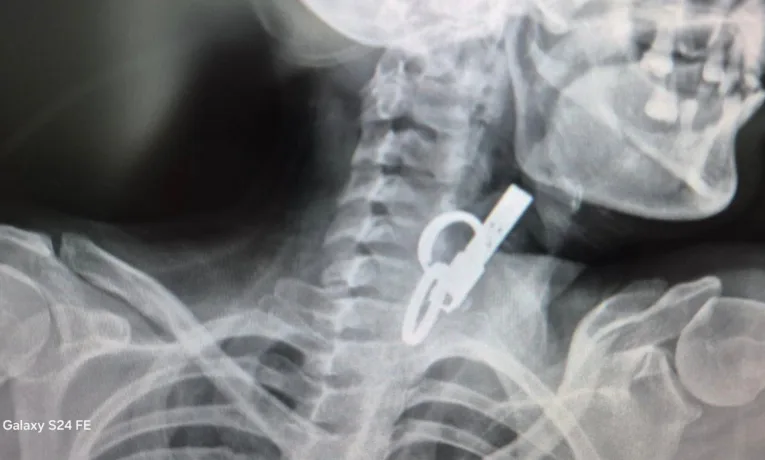

У селищі Гусятин на Тернопільщині лікарі врятували життя 40-річній пацієнтці. З її стравоходу витягнули дверний ключ. Вона його проковтнула, щоб не пускати родичів у хату. До лікарні пацієнтка потрапила в шоковому стані. Медики встигли діагностували причину й оперативно провели операцію за допомогою ендоскопа без жодного розрізу.

«Це дуже показовий випадок, що нам вдалося її врятувати. Як свідчить практика, переважно такі хворі гинуть. Спочатку ми не могли зрозуміти, що застрягло у стравоході. Це були якісь металеві кільця, які стояли зверху, а далі було ще якесь чужорідне тіло. Я здогадався, що це може бути ключ від дверей і почав його обережно витягувати», – розповів Олександр Садовий.

З’ясувалося, що ключ жінка проковтнула, щоб не віддати його родичам і, щоб вони не мали доступ до її помешкання. Лікар додає, що в обласну лікарню у Тернополі не ризикнули везти пацієнтку, оскільки її вже доставили в стані шоку, то жінку просто б не довезли. Рішення про операцію приймали за лічені хвилини.